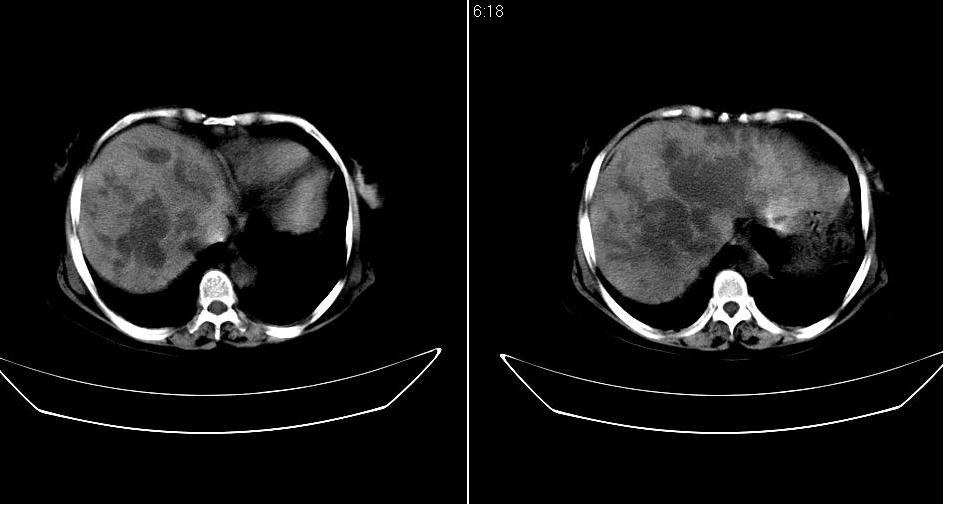

以下是引用守望可可西里在2007-1-20 23:09:00的发言:[br][br] 胰头癌,胆总管梗阻、截断,肝内外胆管重度扩张,肝内边缘部分的圆形低密度病灶多能与扩张的胆管较为连续,暂不考虑转移。病人没有黄疸吗?

以下是引用天南地北在2007-1-20 23:22:00的发言:[br]1:按照肿块的位置及胆总管的形态:考虑胆总管(中下段)癌并肝内胆管扩张,累及胰头。2:不排除胰头癌并肝内胆管扩张。[br]肝内病灶看起来还是扩张的胆管,不考虑转移先。